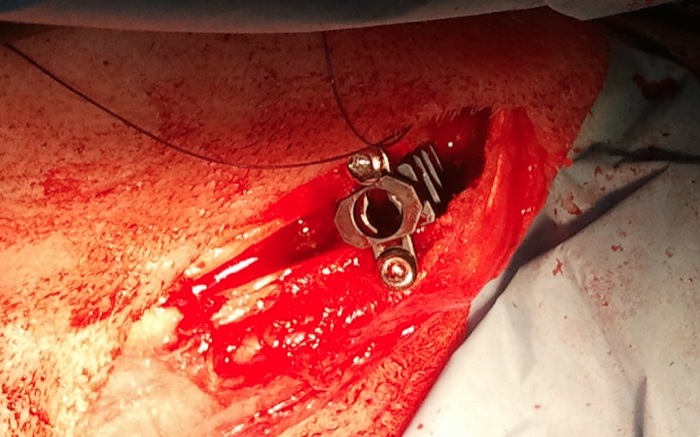

Se cierra la osteotomía, hecha con sierra oscilante y sin guía, tras la colocación en proximal de la celda de 6 mm sujeta con 2 tornillos de 2,7 mm colocados de medial a lateral y algo separados del corte.